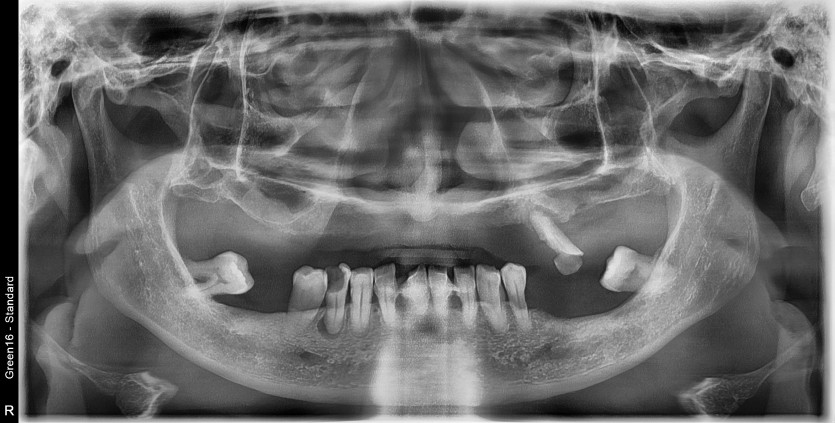

만 53세 전체 임플란트 증례

전체 임플란트 증례입니다.

15개의 임플란트로 완성하였습니다.